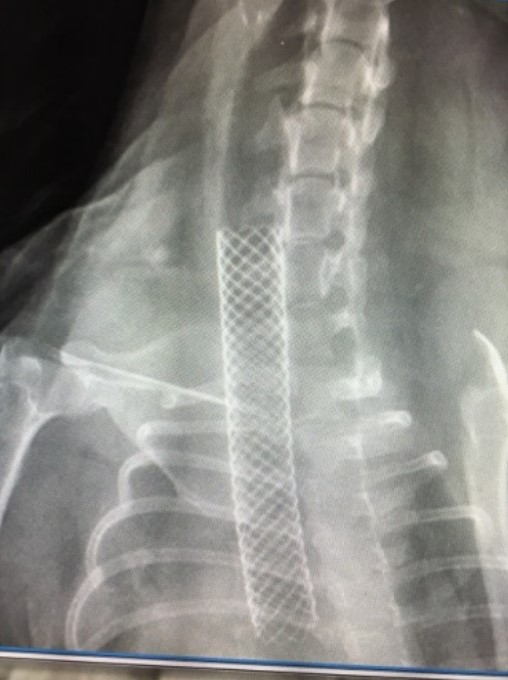

Thoracic radiographs were obtained in Kiley to rule out the presence of preexisting pneumonia and a full bronchoscopy was performed prior to fluoroscopy to grade and assess the degree and type of collapse. There is emerging evidence that the Grade IV collapse may be a different version of the disease and stenting may not be the best approach in these patients. Also, if bronchial collapse is present this may impact the outcome. Bronchial collapse by itself is not a reason to avoid stenting the trachea, but bronchial stents are not well tolerated or effective. Additionally, a wash was performed at the time of stent placement. In one study, endotracheal washes in dogs at the time of stent placement showed that 83% had evidence of inflammation, but surprisingly, 55% of dogs had positive airway cultures, indicating that the normal airway defense mechanisms are impaired in dogs with collapse. Kiley was diagnosed with Grade III intrathoracic tracheal collapse. Under fluoroscopic guidance a tracheal stent was placed spanning the length of the collapse and Kiley was recovered smoothly.

She was kept in clinic overnight to monitor for any complications post-stent placement and then discharged to the owners the following day. She was kept on hydrocodone, prednisone, and trazadone. She was rechecked 2 weeks later. Her cough remained, as it almost always will, but the honking and dyspnea had resolved. This is the goal of stent placement. Kiley continues to do well at home.